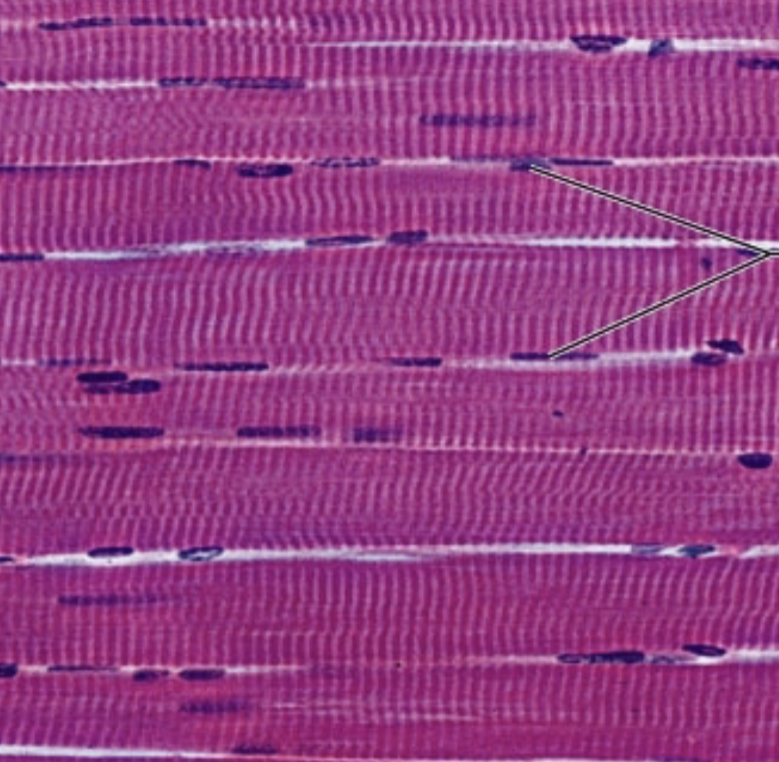

skeletal muscle

Location:

Function:

for skeletal muscle

Location: in the skeletal muscle attached to bones or skin

Function: produce voluntary movement